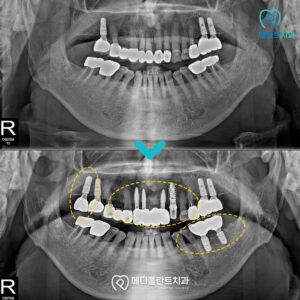

춘천수면임플란트 의식하진정으로 편안하게! 안녕하세요:) 춘천수면임플란트치과 메디플란트치과입니다. 유치가 빠지고 새롭게 자라나는 영구치는 말 그대로 평생 사용해야 하는 치아이기 때문에 한 번 상실하면 다시 자연적으로 회복되기 어렵습니다. 따라서…